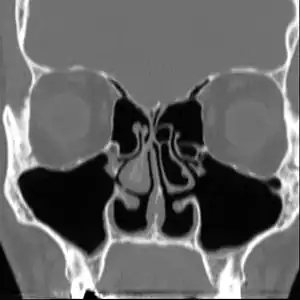

No consensus criteria exist for the diagnosis of ENS and many ENTs will wait a year before diagnosing in hopes the patient accepts the new airflow; it is typically diagnosed by ruling out other conditions, with ENS remaining the likely diagnosis if the signs and symptoms are present.[4][5][9] A "cotton test" has been proposed, in which moist cotton is held where a turbinate should be or in various locations in the nasal passages, to see if it provides relief and an airflow pattern that allows for natural breathing; while this has not been validated nor is it widely accepted, it may be useful to identify which people may benefit from surgery.[4][5][9]

As of 2015, protocols for using rhinomanometry to diagnose ENS and measure response to surgery were under development,[5][9] as was a standardized clinical instrument (a well defined and validated questionnaire) to obtain more useful reporting of symptoms.[9]